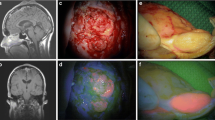

In vitro cultures were established to further explore the potential of SSTR-2 as a meningioma-specific marker in a translational model. After processing the freshly resected material, 11 of 22 cultures (50%) generated 3D cultures after 7 days (Fig. 2, top panel). However, growth decreased after three to four passages. A selection of three cultures named MgG24, MgG26 and MgG27 was characterized in more detail. These cultures originated from three female patients with a mean age of 65.7 years (range 60–77; SD 9.8). All meningiomas were WHO grade I, with one transitional and two meningothelial meningiomas (Fig. 2, middle panel). Two meningiomas were located at the convexity and one at the skull base (Fig. 2, bottom panel).

Top panel shows micrographs of 3D meningioma cultures with × 10 magnification. Middle panel depicts micrographs of H&E stained original patient tumour at × 40 magnification. Bottom panel are gadolinium-enhanced MRI scans. 3D cultures showed aggregated cell formation into a sphere. H&E stained tumour samples confirmed the diagnosis of meningioma in all three cases. MRI scans revealed meningiomas at the convexity and skull base

SSTR-2 expression was determined on original patient tumours and 3D cultures of the three established cultures. All patient tumours were strongly positive for SSTR-2 at the cell membrane (Fig. 3, top panel). However, of the dissociated 3D cultures, only MgG24 and MgG26 are SSTR-2 positive with a cell membranous staining. It should be noted that not all cells are (equally) positive in both cultures: some cells show no or weak SSTR-2 positivity, whereas in other cells, the staining is strongly positive (Fig. 3, bottom panel).

Top panel depicts micrographs from primary tumour stained for SSTR2 at × 10 magnification. Bottom panel shows micrographs of dissociated cells cultured as 3D and stained for SSTR2 at × 40 magnification. Patient material showed SSTR-2 membrane staining in all tumours. Two of three dissociated 3D cultures revealed SSTR-2 positive membranous staining in a fraction of cells